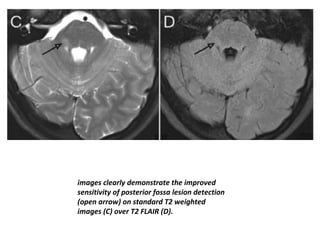

images clearly demonstrate the improved

sensitivity of posterior fossa lesion detection

(open arrow) on standard T2 weighted

images (C) over T2 FLAIR (D).

images clearly demonstratethe improved sensitivity of posterior fossa lesion detection (open arrow) on standard T2 weighted images (C) over T2 FLAIR (D).